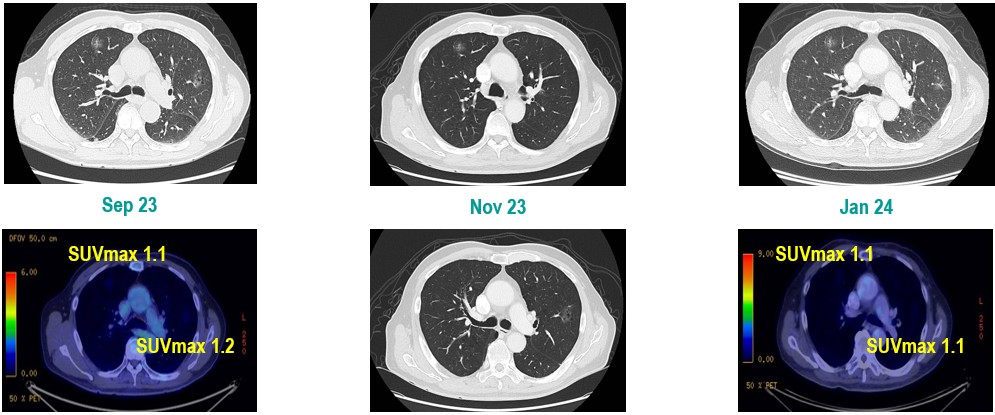

CT及PET-CT随访(2023年11月、2024年1月):评估新辅助治疗效果,右下肺叶肿块缩小,右肺门淋巴结代谢活性消失,右肺上叶结节稳定但代谢活性降低,左肺上叶及双侧磨玻璃样病变稳定。

新辅助治疗:患者接受4周期新辅助化疗联合免疫治疗(培美曲塞、顺铂、纳武利尤单抗),治疗后影像学显示肿块缩小,代谢活性降低。

手术治疗:2024年1月行右肺下叶切除术及右肺上叶楔形切除术,术中病理显示右肺下叶为腺癌伴SCLC灶,右肺上叶为腺癌。术后病理分期:右肺下叶腺癌为ypT2aN0M0(IB期),伴SCLC灶,考虑为治疗后转化;右肺上叶腺癌为ypT1bN0M0(IA2期)。